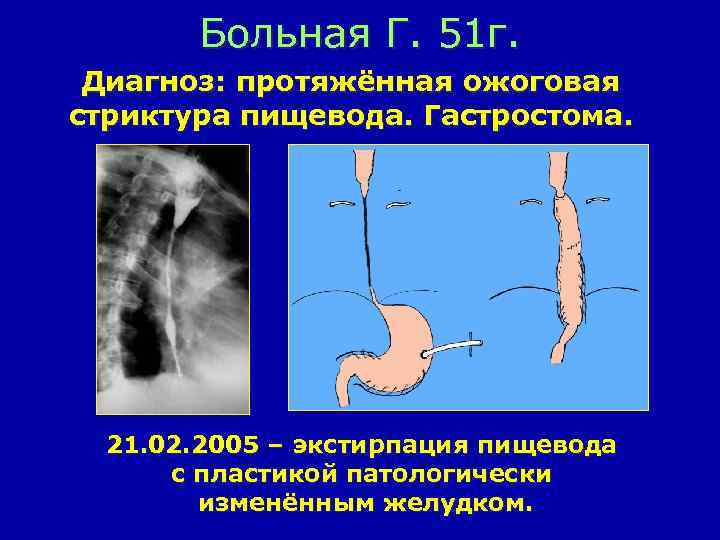

Больная Г. 51 г. Диагноз: протяжённая ожоговая стриктура пищевода. Гастростома. 21. 02. 2005 – экстирпация пищевода с пластикой патологически изменённым желудком.

Схема пластики пищевода желудочной трубкой